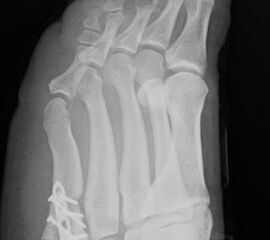

Abb. 3a, b: Präoperatives (a) und postoperatives (b) Röntgenbild bei Korrektur einer Typ I Deformität durch eine Exostosenabtragung.

Abb. 4a, b: OP Bilder bei lateraler Exostosenabtragung. Nach Hautschnitt ist die teilweise rupturierte laterale Gelenkkapsel erkennbar (a) mit Bursagewebe. Nach Resektion der Bursa und Abtragung der Exostose zeigt sich eine spongiöse Fläche (b) vor dem Wundverschluss.